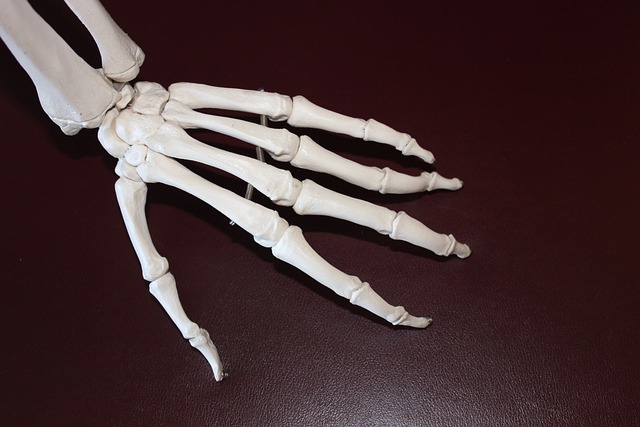

퇴행성 관절염은 관절의 연골이 서서히 손상되어 발생하는 만성적인 질환으로, 주로 노인이나 중년에 많이 발생합니다.

□ 통증 : 가장 흔한 증상으로 관절이 닳아서 생기는 통증입니다. 이 통증은 활동으로 인해 악화되며, 휴식을 취하면 완화되기도 합니다.

□ 움직임의 제한 : 관절의 변형이나 통증으로 인해 움직임이 제한될 수 있습니다. 이로 인해 일상생활에 불편함을 경험하게 됩니다.